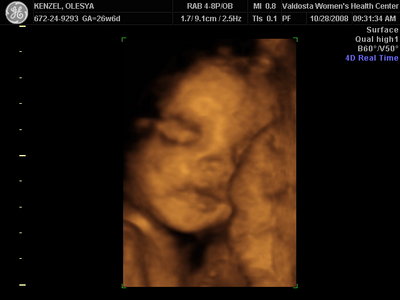

Ксюнь, а мы вообще не поняли. Она на всех фотках разная, да еще размытость такая. Пуповина то на носу болталась, то руками-ногами закрывалась. Главное что четкости нет совсем. Лоб у мужа тоже большой, а носы и губы зачастую на 3Д-4Д выходят разамазанно-пухло-приплюснутыми Поставлю для наглядности фотку моей средней-Джианки с 3Д УЗИ, там видно черты намного лучше и она на себя ту похожа сейчас, хотя родилась мне совсем на фото УЗИ не казалась похожей.

KENZEL,OLESYA_3.JPG [ 56.84 КБ | Просмотров: 1428 ]

Еще одна Джианнка:

KENZEL,OLESYA_5.JPG [ 60.02 КБ | Просмотров: 1513 ]